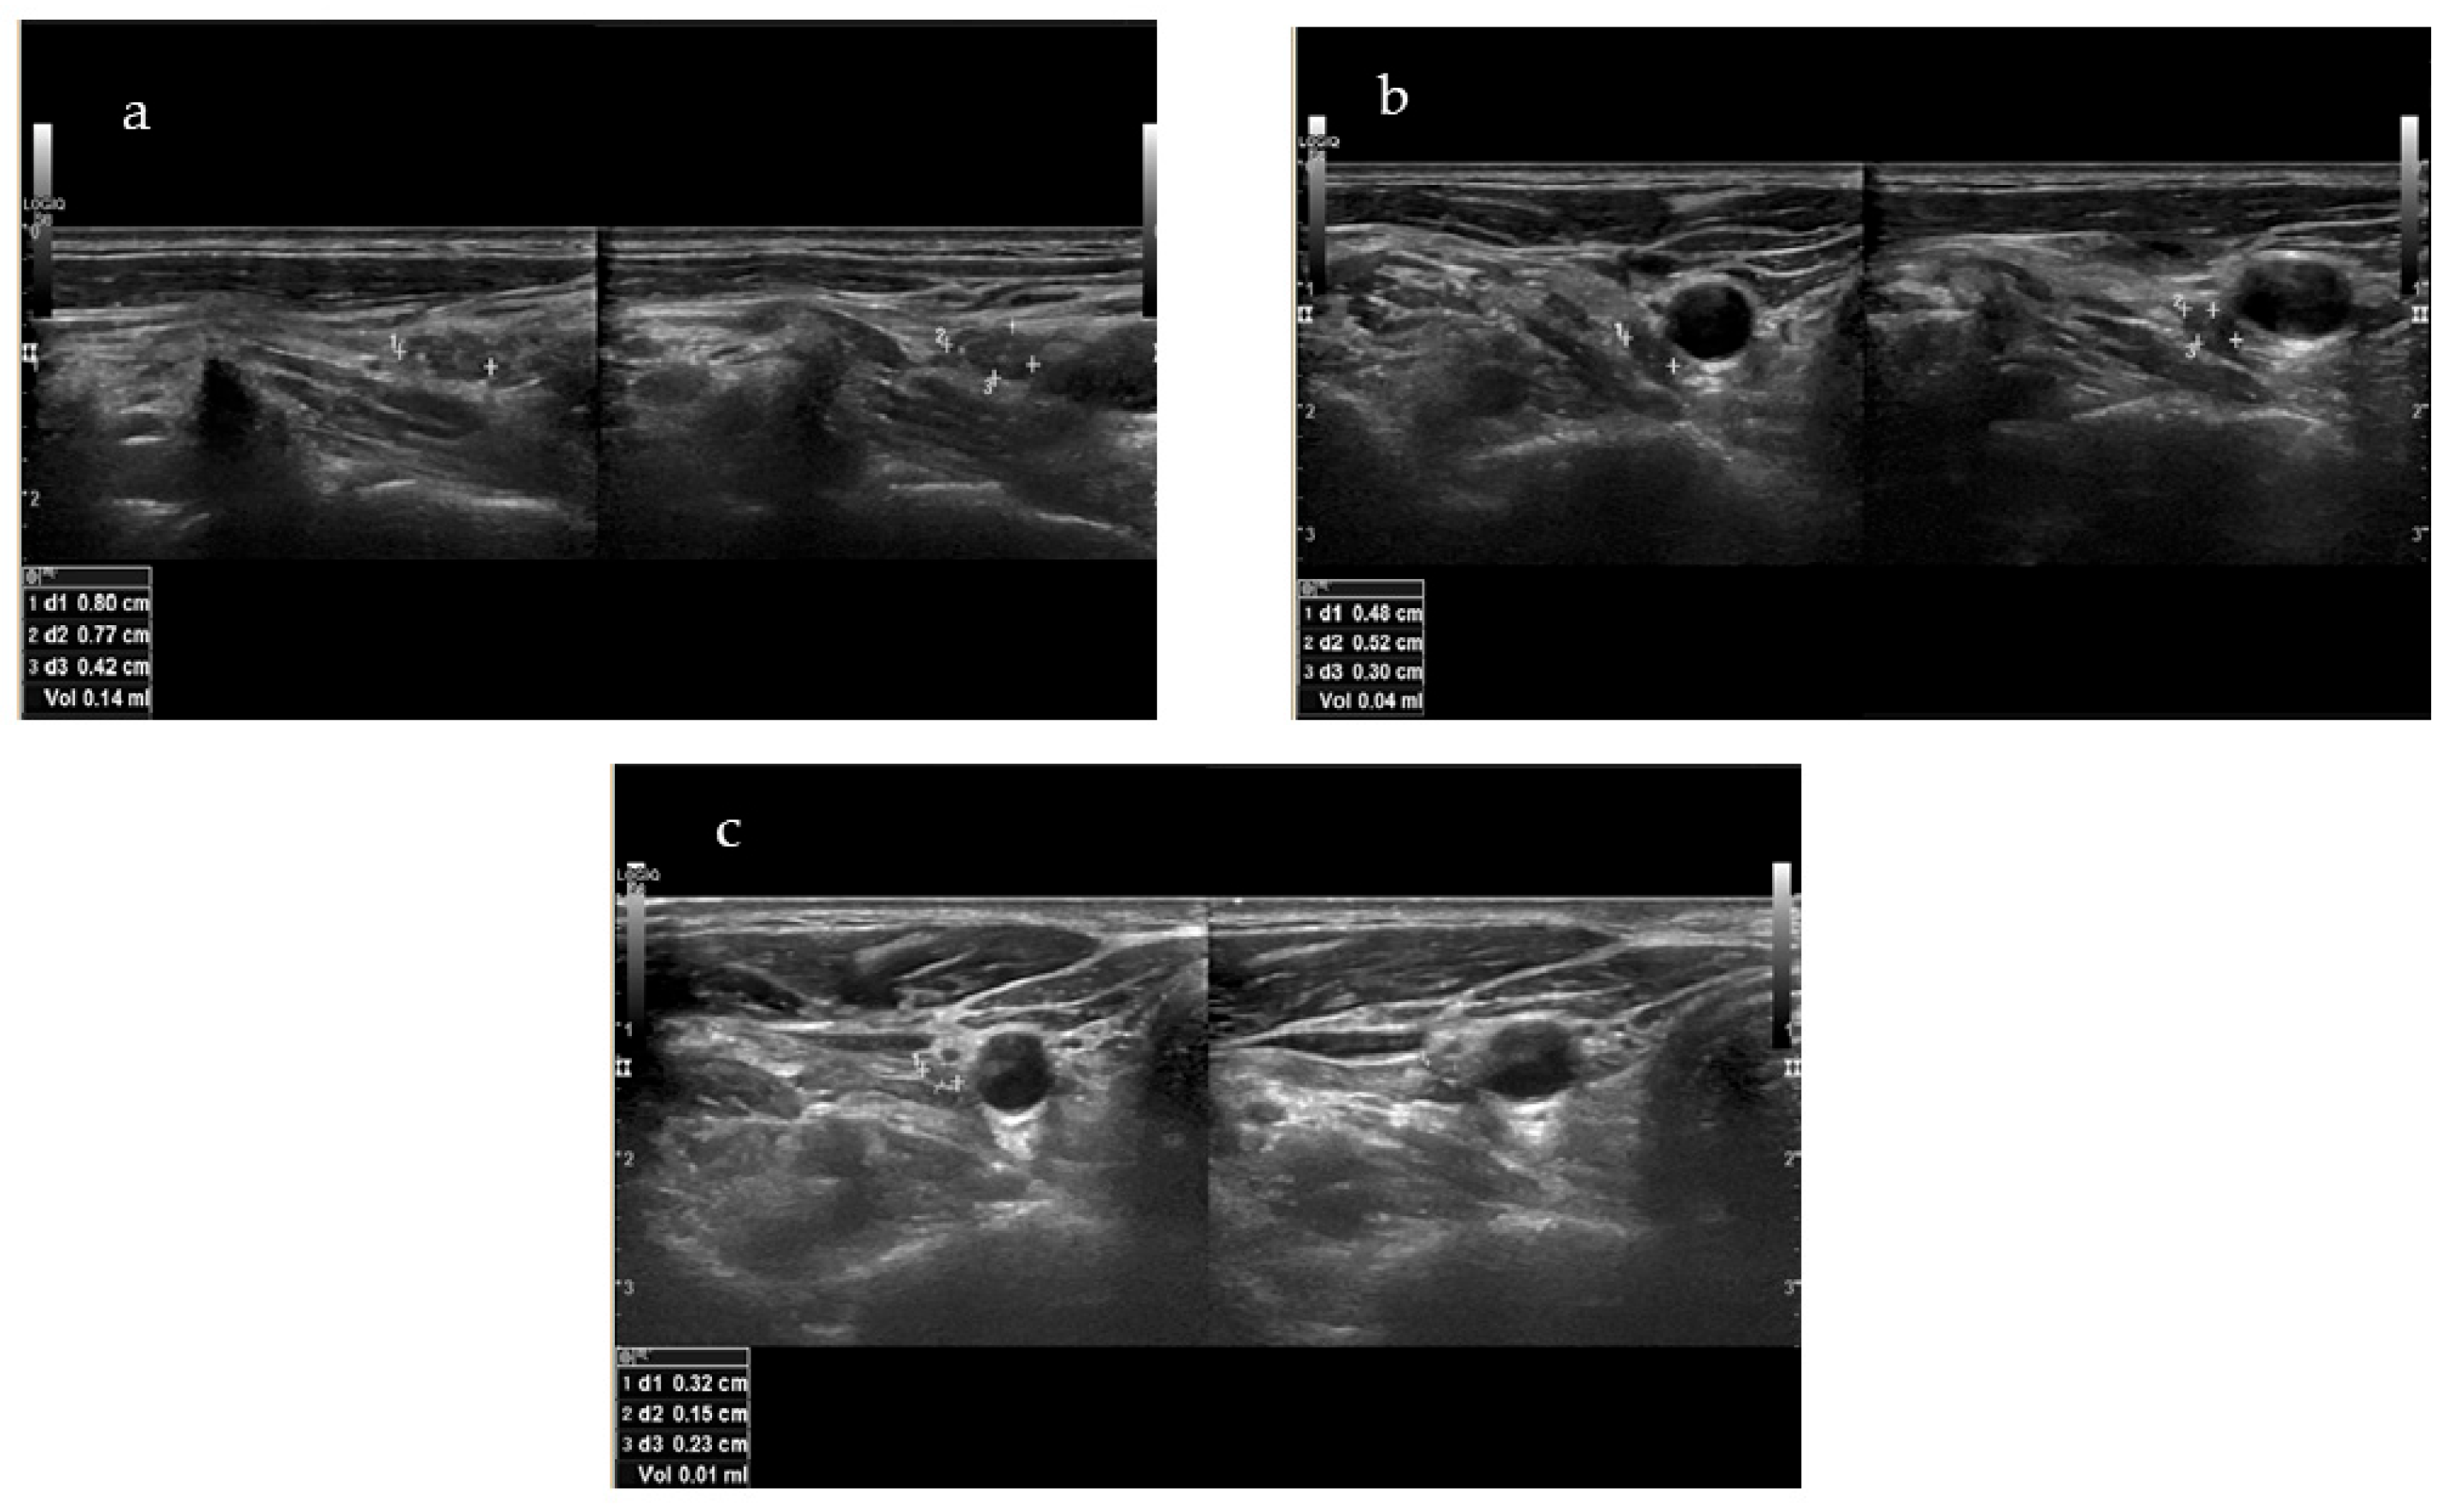

Indicatively, the targeted lesion of patient No4 (i.e., the patient with the longer f-up) is depicted in Figure 2a–c, before RFA, at one month after RFA, and at the final f-up 24 months after RFA, respectively. Out of 14 lesions that were treated, 2 (14.3%) were no longer visible in the U/S.

Figure 2.

(a–c) Targeted lesion of patient No4 before RFA (a), at one month after RFA (b) and at final f-up 24 months after RFA (c).